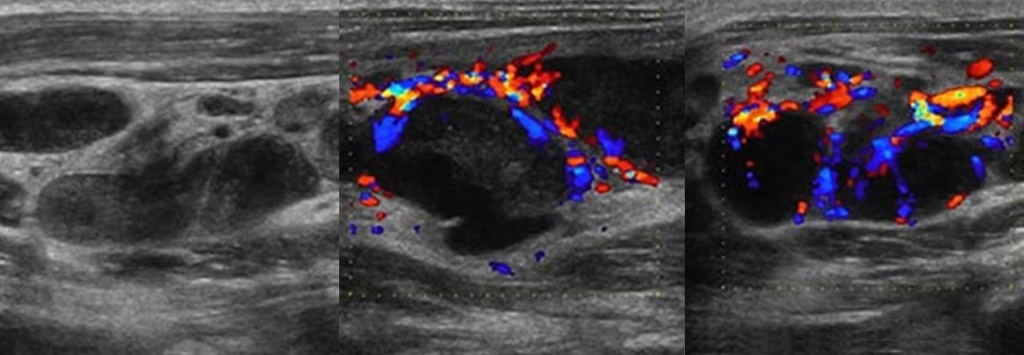

УЗИ лимфоузлов при лимфоме Ходжкина

Раздел: Образы вокруг